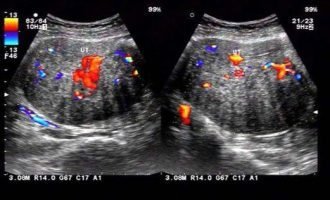

前期咨詢與身體評估:通過線上或線下方式與格魯吉亞生殖中心聯(lián)系,提交基礎(chǔ)體檢報告(如AMH、性激素六項、B超等),醫(yī)生評估卵巢功能后制定個性化促排方案。

赴格魯吉亞入周:抵達后進行身體復(fù)查,開始促排卵治療。期間定期監(jiān)測卵泡發(fā)育情況,適時注射破卵針。